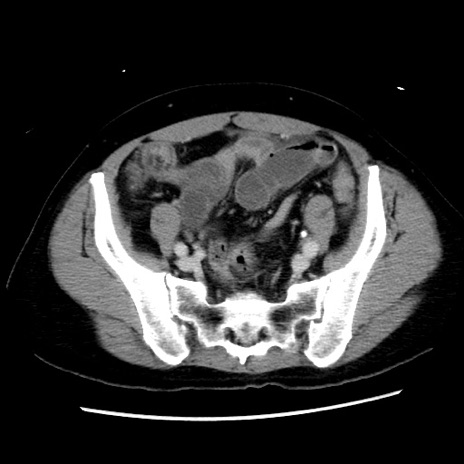

症例10(横断像)

【症例】 50歳代女性

【主訴】 腹痛

【現病歴】前日生レバーを食べた。今朝に排便あり。 昼前に突然発症の腹痛を生じ、当院救急外来を受診した。

【既往歴】 子宮筋腫にてで子宮全摘後

【身体所見】 意識清明、腹部:平坦、軟、下腹部やや左を中心に圧痛・反跳痛あり、筋性防御あり

【データ】WBC 7800、CRP 0.07